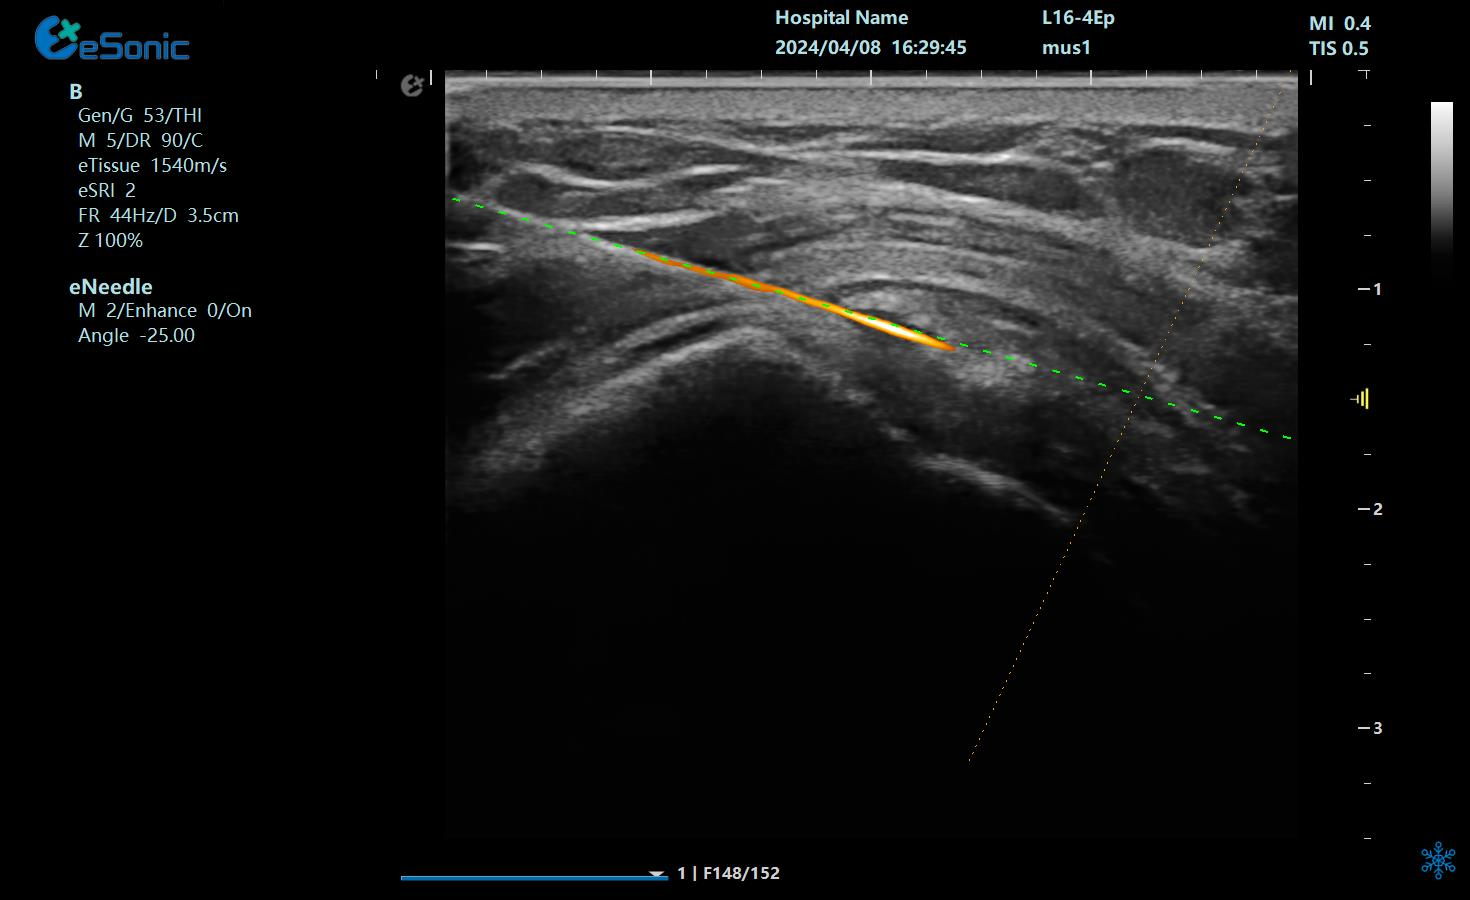

治疗中使用穿刺针智能Map和无磁导航技术

在超声图像中,穿刺针和钙化灶的显示都为强回声,常规的超声引导穿刺即使增强了穿刺针的显示仍不能有效地区分针尖和钙化灶,可能导致对穿刺部位的判断失误,往往比较依赖于医生的经验穿刺到钙化灶。

1?? ?染色暴击?:给穿刺针穿上"荧光赛博战衣"(智能Map一键上色),钙化灶当场被标记成"通缉犯",超声屏秒变科幻大片!

2?? ?导航开挂?:针尖偏转0.1°?无磁导航立刻甩出"激光瞄准镜",实时画出钙化灶的投降路线图!